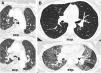

Expiratory CT scan is a complementary technique of inspiratory CT that provide valuable physiological information and may be more sensitive to detect air trapping than pul-monary function tests. It is useful in many obstructive airway diseases, including obliterative bronchiolitis, asthma, Swyer-James syndrome, tracheomalacia, hypersensitivity pneumonitis and sarcoidosis. In obliterative bronchiolitis, expiratory CT scan may be the only imaging technique that shows abnormalities in the early phase of disease. In order to obtain a good quality study, we should explain the procedure to the patient, use precise instructions and do some practice before image acquisition. Here we describe strategies to optimize the techni-que and propose an algorithm that help in interpretation of imaging findings in patients with obstructive airway disease.